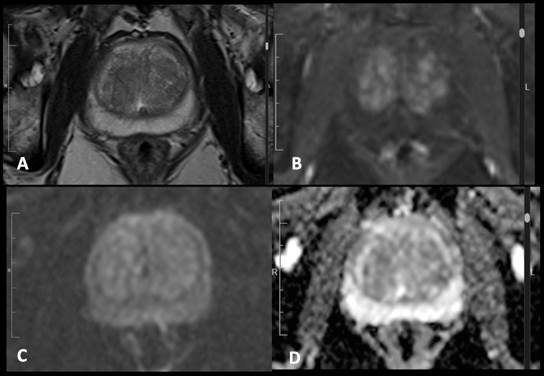

observador 3). Estos revisaron los estudios que cumplieron los criterios de inclusión (paciente con sospecha de carcinoma de próstata y RM con adecuados parámetros para su evaluación) mediante un visor de imágenes médicas (Hiruko, IMEXHS, Bogotá, Colombia). Calificaron las imágenes con los criterios principales del PI-RADS v. 2.1, consignaron los resultados en la herramienta de recolección descrita y emitieron una clasificación final para cada caso. En las Figs. 2, 3, 4, 5 y 6 se muestran ejemplos de las imágenes obtenidas y evaluadas según la clasificación PI-RADS v. 2.1.